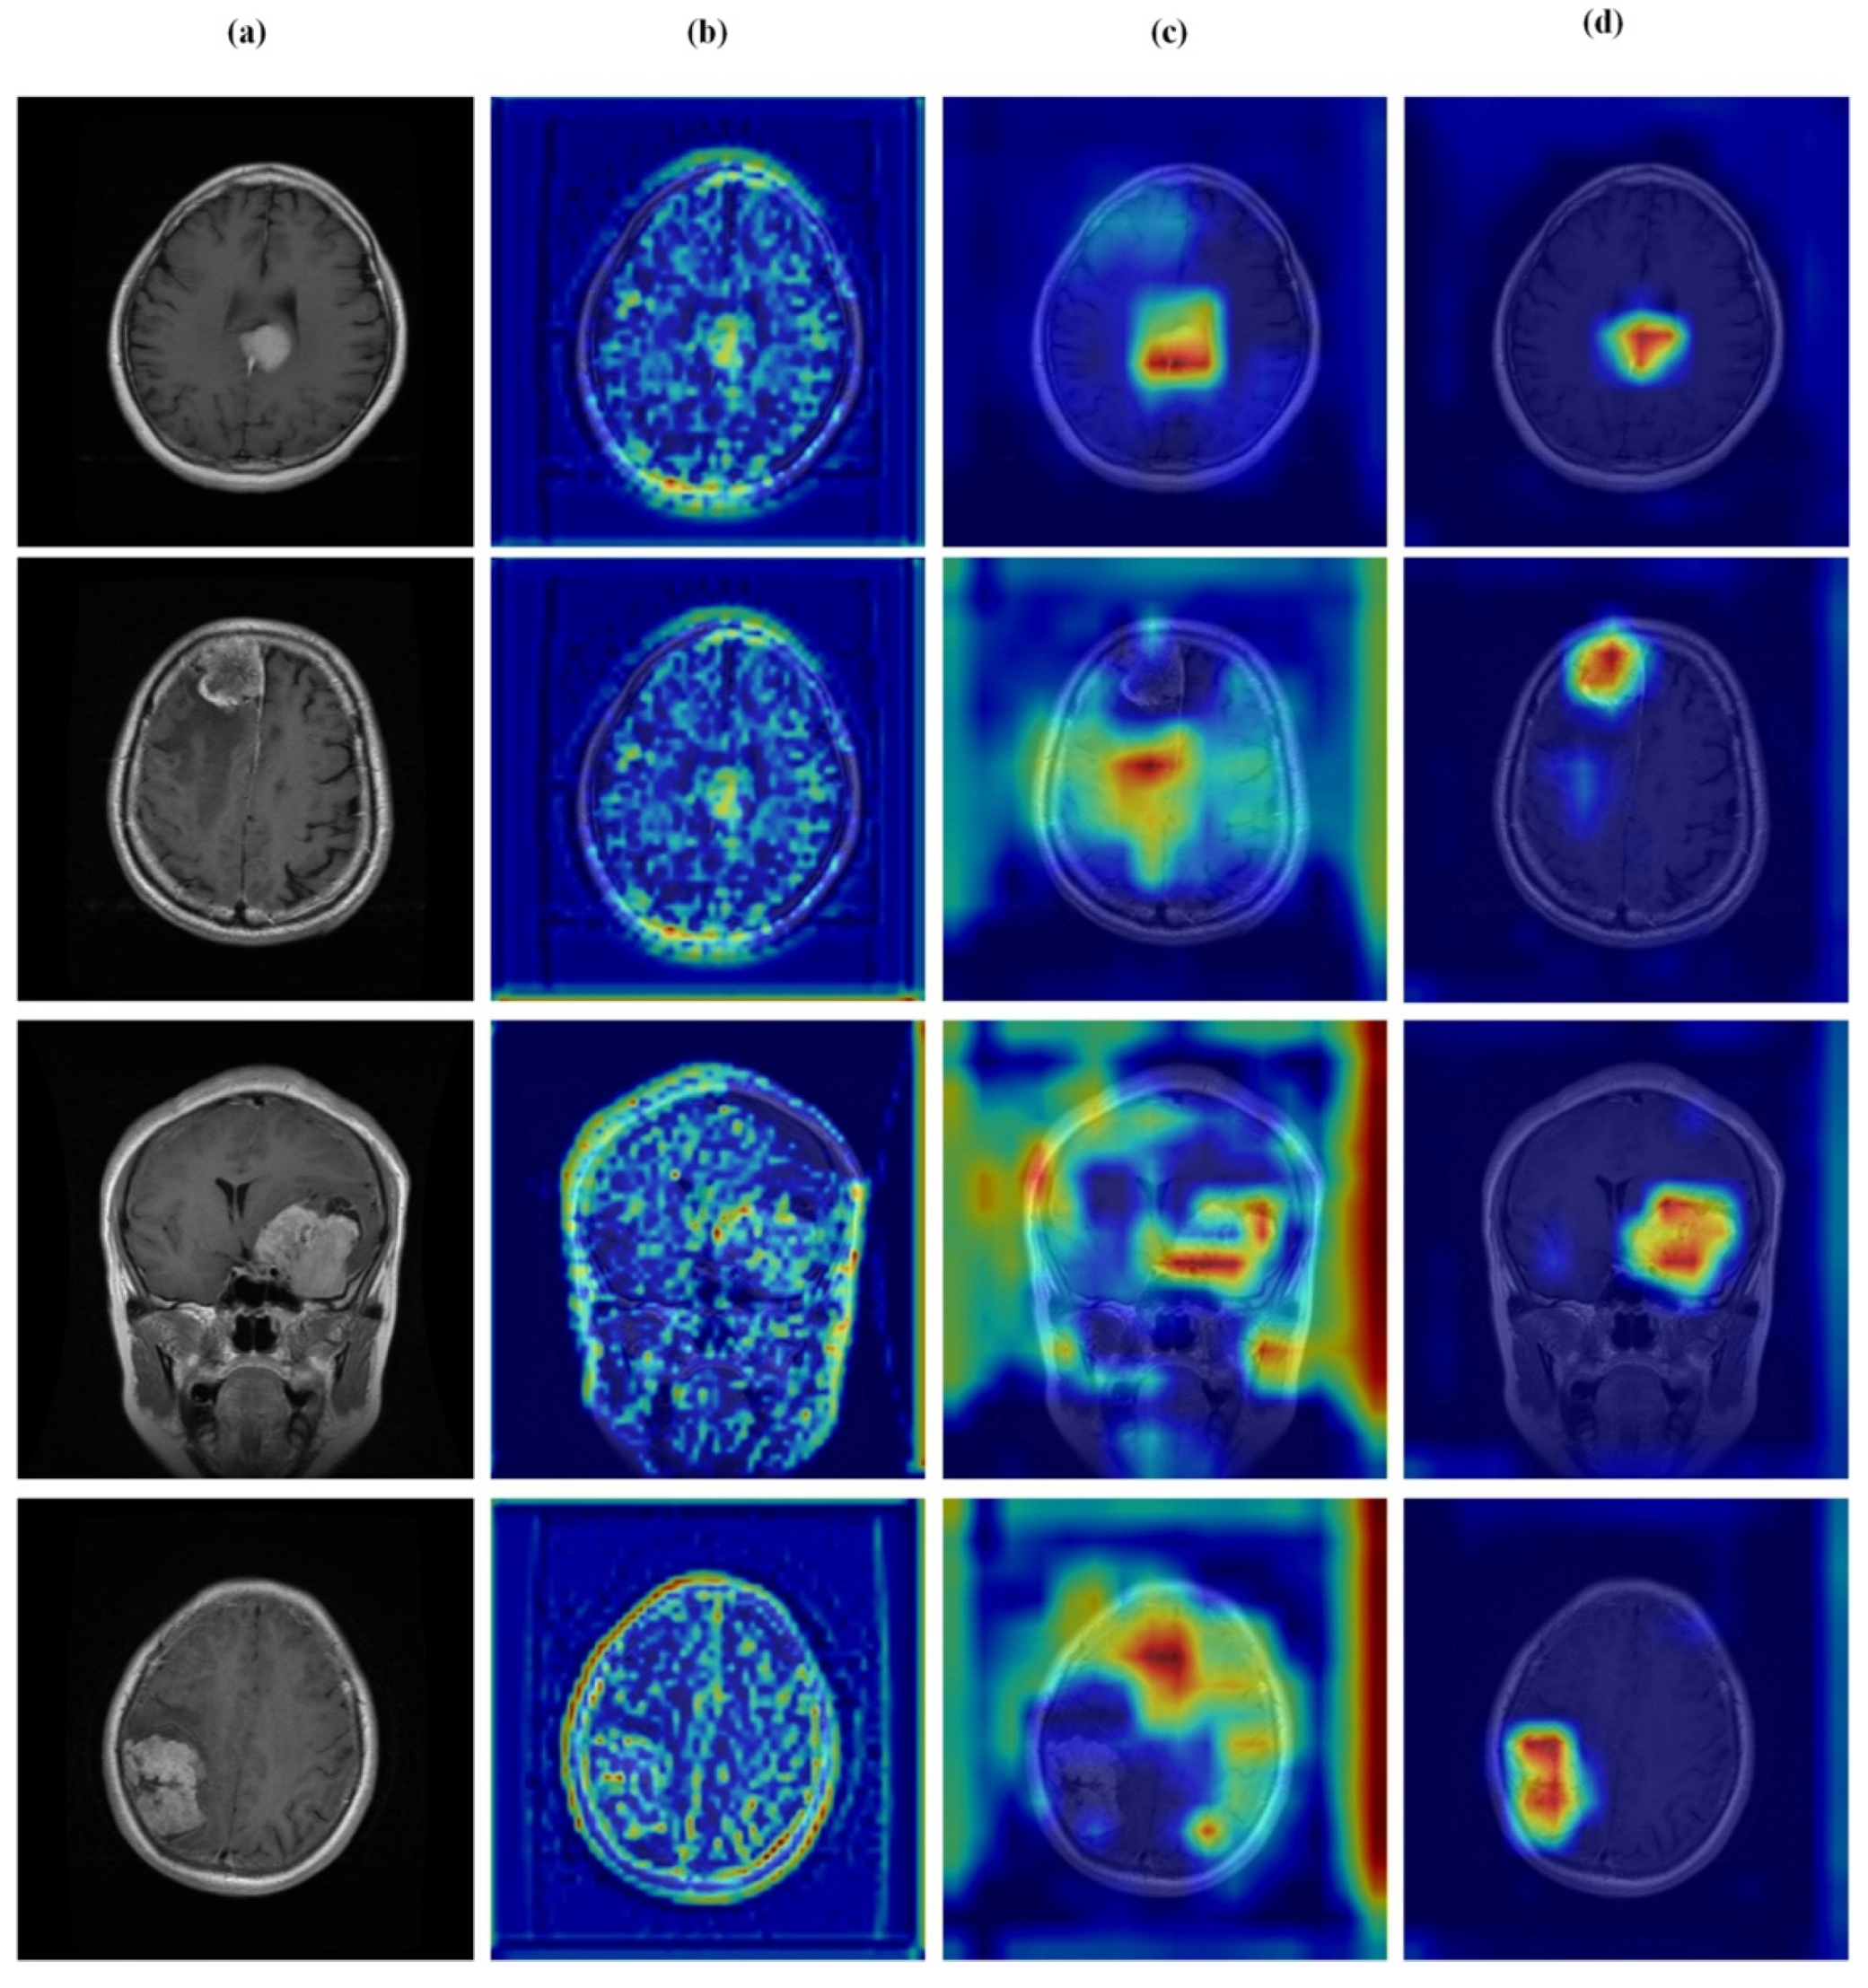

Visual inspection of the segmentation outputs (Figure 10) demonstrates the model’s capability to accurately delineate tumor boundaries across diverse tumor types and imaging conditions. The model successfully handles variations in tumor size, shape, and location, producing precise segmentation masks that closely align with ground truth annotations.

Figure 10.

Random test set predictions. Columns: (a) input image, (b) ground truth mask, (c) predicted mask, and (d) overlay. Rows (true → predicted): (1) no tumor → no tumor, (2) glioma → glioma, (3) meningioma → meningioma, and (4) pituitary → pituitary.

While the model demonstrates strong overall performance, certain challenging cases remain difficult. As shown in Figure 11, these include misclassification between glioma and meningioma (row 1) and under-segmentation of tumors with faint boundaries (row 2). Such failures typically occur when tumors exhibit overlapping intensity profiles, low contrast with surrounding tissue, or ambiguous morphological features.

Figure 11.

Challenging test set cases. Columns: (a) input image, (b) ground truth mask, (c) predicted mask, and (d) overlay. Rows (true → predicted): (1) glioma → meningioma (misclassification) and (2) pituitary tumor with under-segmentation.